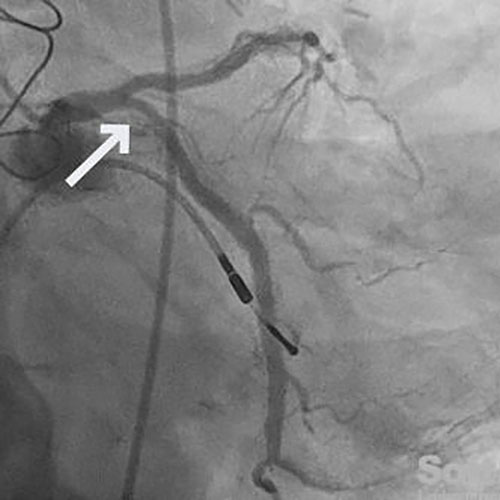

61-year-old male with hypertension, hyperlipidemia, and prior inferolateral STEMI, status post PCI ×2 to the proximal LCx, with residual 70% mid-LAD (D2) disease managed medically.